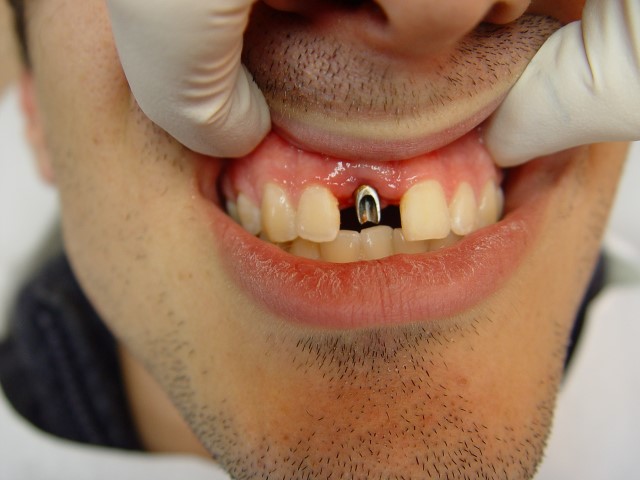

מבנה מותאם לשתל החדש

צילום השתל עם המבנה לקראת השיקום

סיום הטיפול